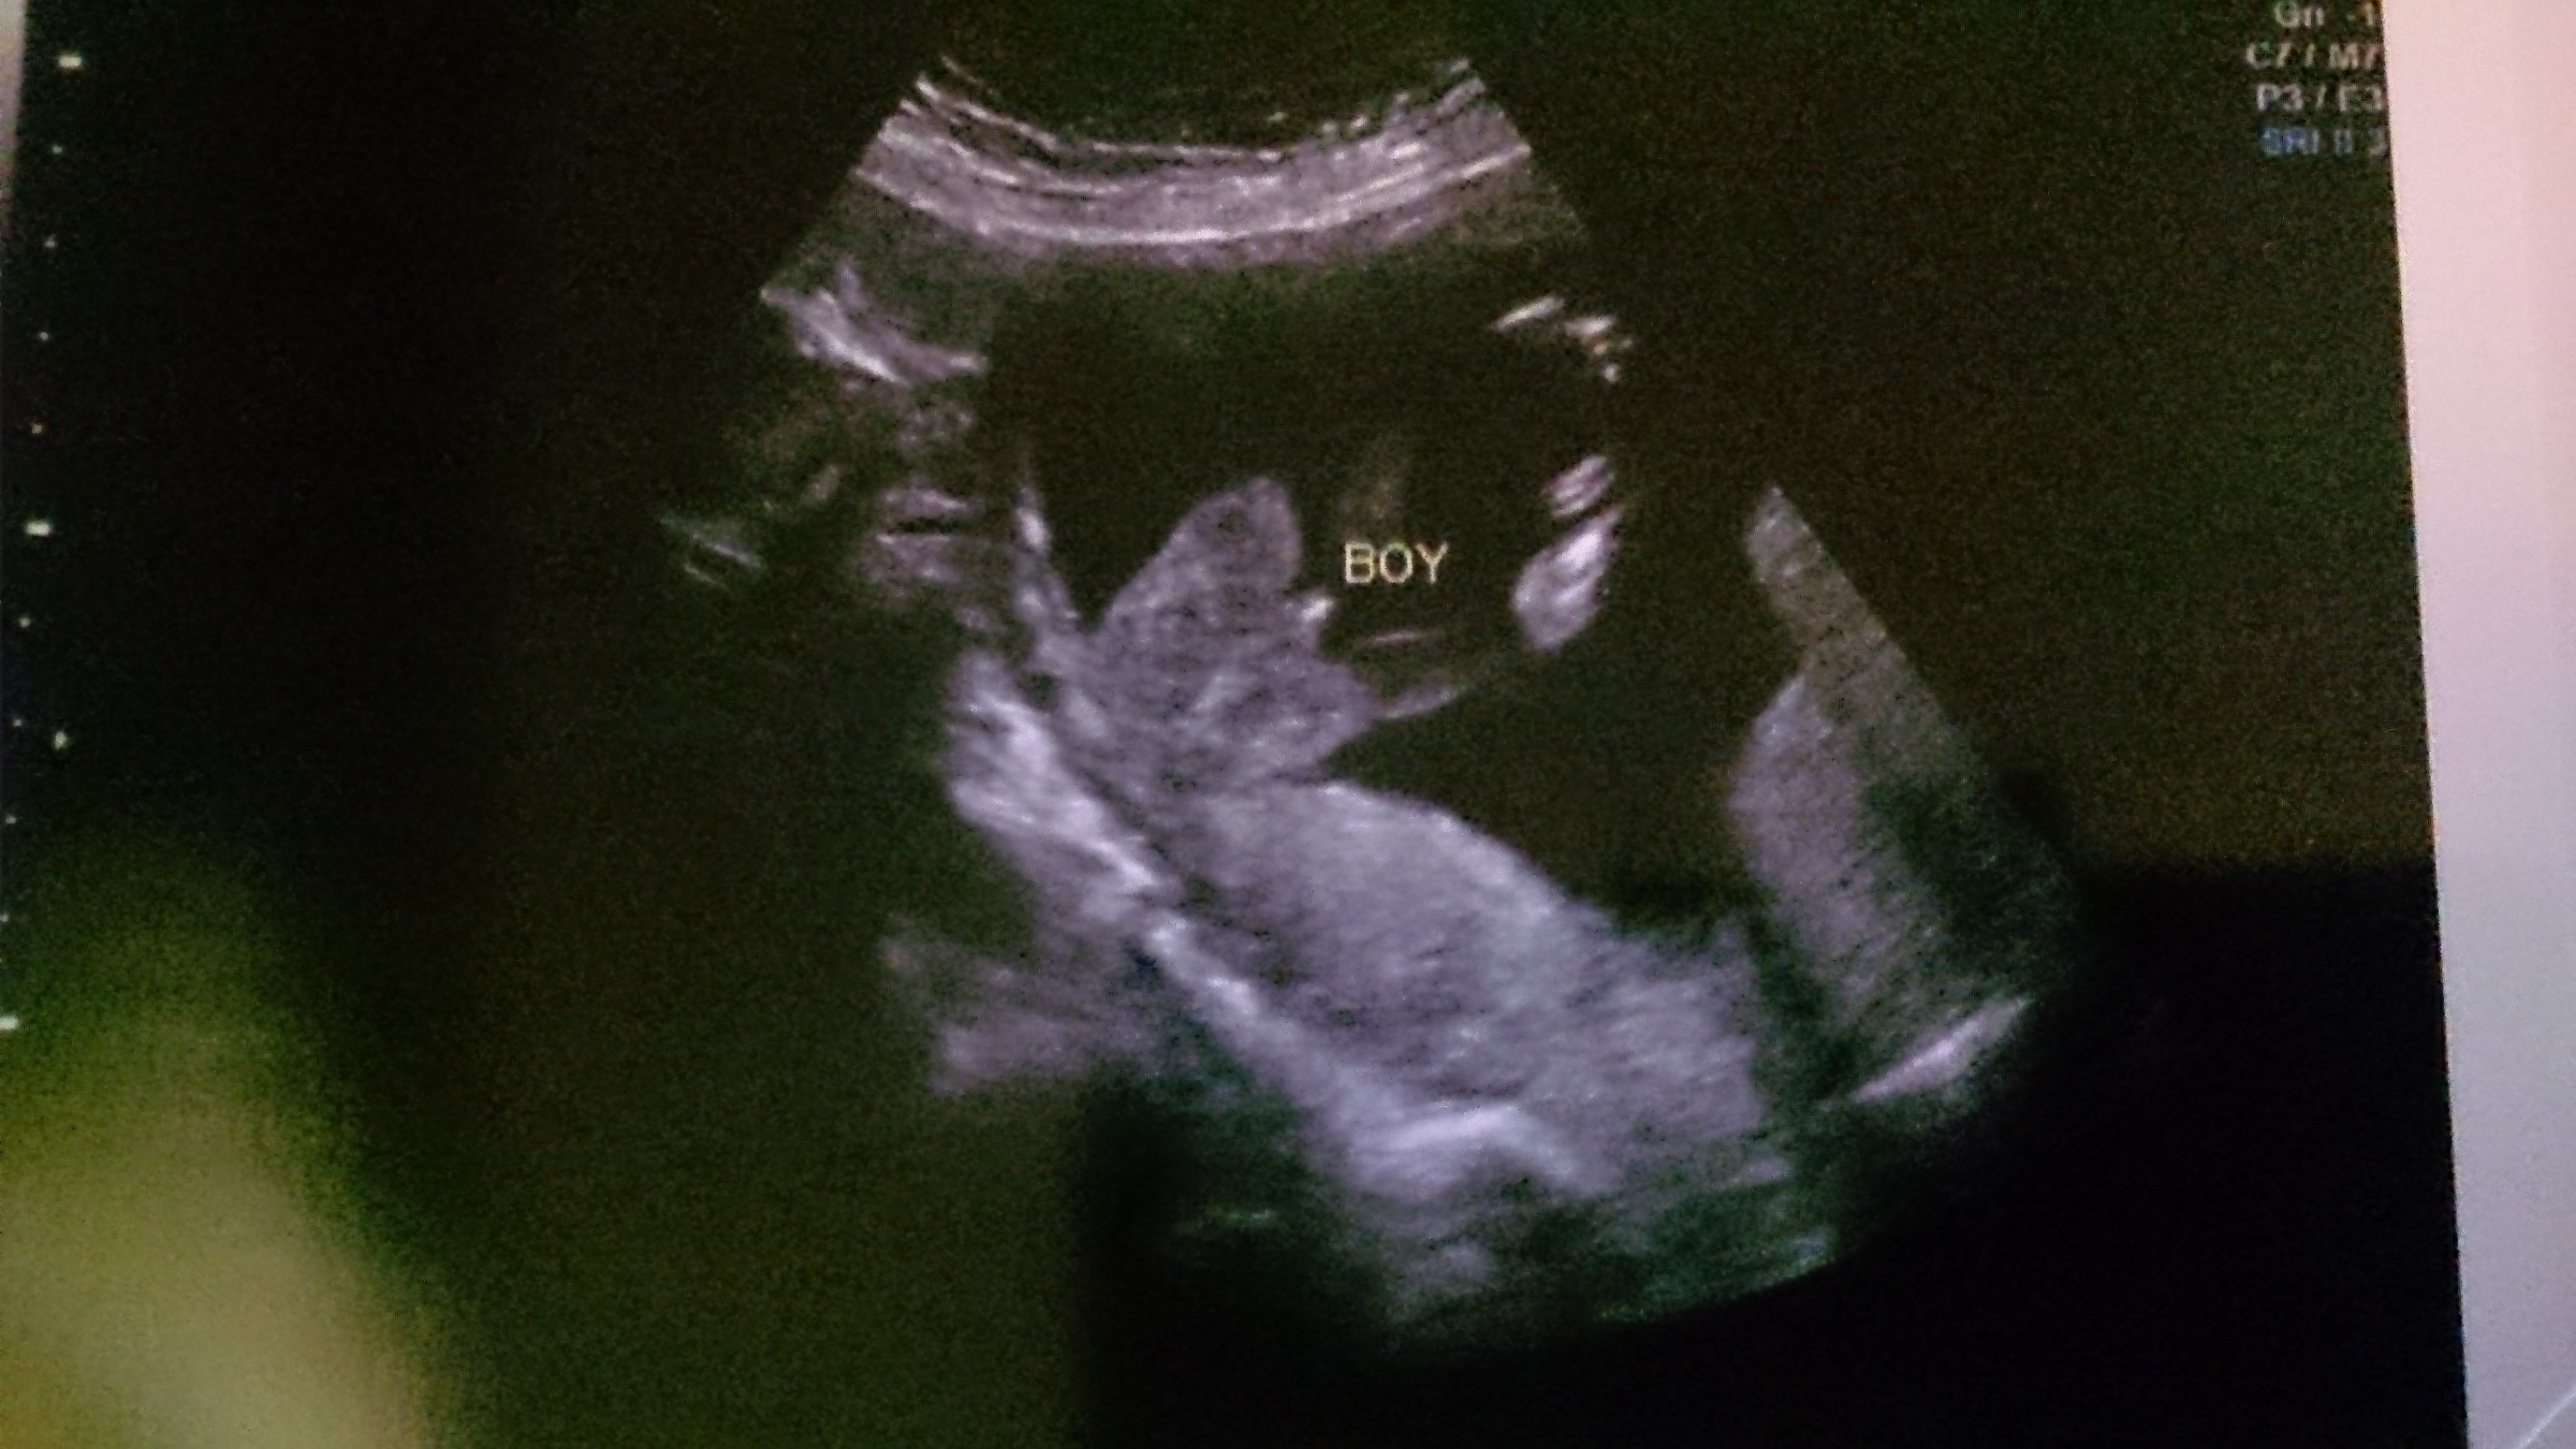

Pochwalę się moimi zdjęciami z usg - nie są tak wyraźne jak u Was, ale i tak wczorajsza wizyta wzruszyła mnie na maxa [emoji4]. Wg usg wychodzi nam 12 tc. Wzrost - 4,8 cm.

Zobacz załącznik 788313Zobacz załącznik 788314